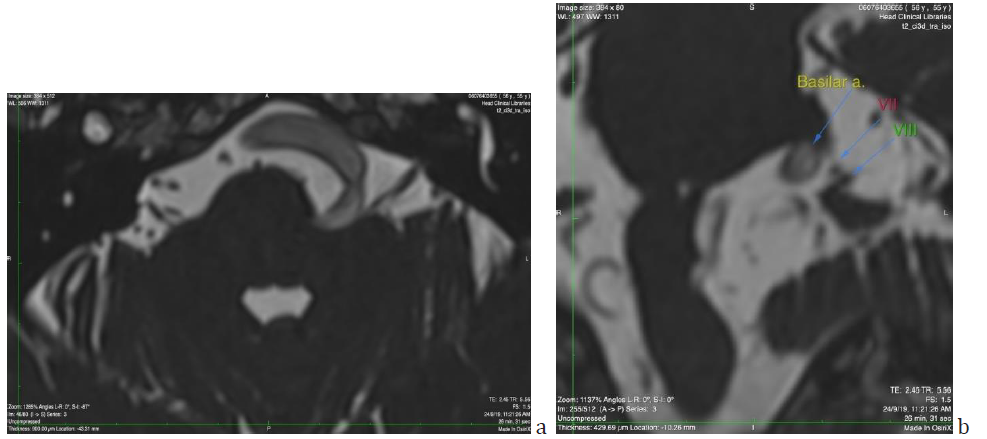

Figure 3: a) Axial T2-tse sequence showing the mass effect on the medulla oblongata (arrow) and the asymmetry of vertebral arteries, with left dominance. b) Axial section of Brain MRI (T2ci3d sequence) showing the basilar artery at the midpons level, assuming a lateral position at the margin of the clivus (arrow). The diameter of the artery is 5.12mm). Note the similarities with fig 2, imaging done sixteen years earlier.

Figure 5: a) Axial section of Brain MRI (T2 ci3d sequence) showing the proximity of vertebrobasilar artery tortuous pathway with the root of the eighth cranial nerve. b) Coronal reconstruction of the same image, picturing in detail the relationship among the BA the VII and VIIIth cranial nerves. The distance between BA and VIIIth nerve was measured 1.8mm.

According to Smoker’s criteria BA reaches the lateral border of the clivus (Laterality criterion grade 2) (Figure 3b). The level of bifurcation reaches the floor of the third ventricle (grade 2). The dimension of the BA at the midpons level is 5.12mm. (Smoker’s criteria for ectasia >4.5mm). In the present case the vertebrobasilar system is tortuous and elongated with moderate ectasia. No signs of intraluminal thrombi are found. There is a mass effect on the brainstem and a dominance of the left vertebral artery (side to side difference of vertebral artery diameters was >0.3mm) [7] (Figure 3a).

Figure 5 shows the proximity of the vertebrobasilar artery to the eighth cranial nerve. The question arising is whether SSNHL episodes could be attributed to compression of the nerve root by the artery. The distance between the artery and the nerve has been measured to be 1.8 mm.